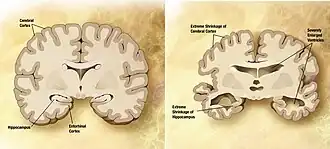

Comparison of a normal aged brain (left) and a brain affected by Alzheimer's disease

Dementia becomes more common with age.[47] About 3% of people between the ages of 65 and 74, 19% of those between 75 and 84, and nearly half of those over 85 years old have dementia.[48] The spectrum ranges from mild cognitive impairment to the neurodegenerative diseases of Alzheimer's disease, cerebrovascular disease, Parkinson's disease and Lou Gehrig's disease. Furthermore, many types of memory decline with ageing, but not semantic memory or general knowledge such as vocabulary definitions. These typically increase or remain steady until late adulthood [49] (see Ageing brain). Intelligence declines with age, though the rate varies depending on the type and may, in fact, remain steady throughout most of the human lifespan, dropping suddenly only as people near the end of their lives. Individual variations in the rate of cognitive decline may therefore be explained in terms of people having different lengths of life.[50] There are changes to the brain: after 20 years of age, there is a 10% reduction each decade in the total length of the brain's myelinated axons.[51][52]